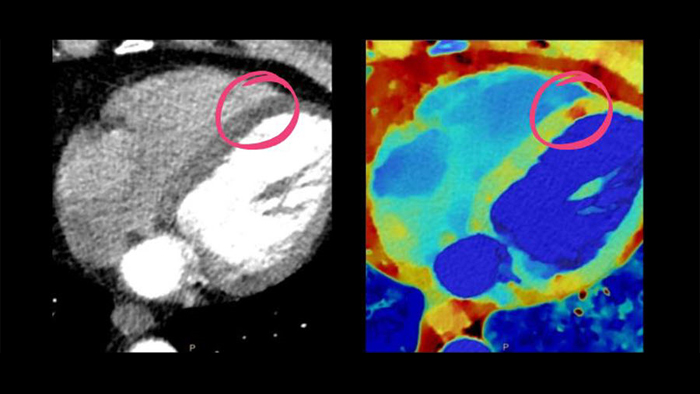

Spotlight on: Cardiac CT (Spectral CT 7500)

See beyond routine cardiac imaging with the additional clinical information of Spectral CT for advanced cardiac applications. Learn how the Spectral CT 7500's "Always On" Spectral CT workflow helps you meet the needs of all your patients with zero compromises.

Spectral CT 7500

Unlock the full potential of CT as a non-invasive cardiac diagnostic tool.